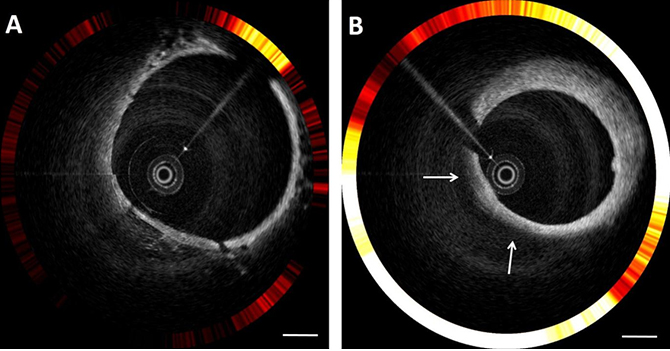

광단층/근적외선 형광 분자영상(OCT/NIRF) 기법은 현재 임상에서 널리 사용되고 있는 광단층 영상기법(OCT)을 통해 혈관의 구조적 정보를 얻음과 동시에 형광 신호를 방출하는 활성화 근적외선 형광 보고자(activatable near-infrared fluorescent probe)로 혈관 내 동맥경화반의 분자적인 정보를 획득하는 기법이다. 본 연구팀에서는 OCT/NIRF 카테터 시스템을 세계최초로 개발하고 임상적용이 가능하도록 2세대 고속 OCT/NIRF 카테터 시스템으로 개선하여 보고한 바 있다. 특히 인체내 허가된 근적외선 형광 물질인 indocyanine green (ICG)가 염증이 심한 지질 성분에 붙는 특성을 이용하여 동맥경화 유도 토끼를 대상으로 ICG를 정맥주사 하였으며, 20분에 OCT/NIRF 카데터 시스템을 통해 이미지를 획득하였다. 그림 2에서 보는 바와 같이 OCT로 관찰된 동맥경화반에서 강한 NIRF 신호가 관찰되는 것을 볼 수 있으며, 같은 부위에 대한 조직 절편에서 면역조직화학염색 검사를 통해 대식세포 및 지방의 분포와 근적외선 형광영상 신호의 위치가 일치됨을 확인하였다. 현재 이 시스템을 이용한 임상시험도 준비하고 있어 향후 고위험 관상동맥 질환환자에서 동맥경화반의 파열 위험도를 미리 진단할 수 있는 새로운 장을 열수 있을 것으로 기대된다.

그림 2. 2세대 고속 OCT/NIRF 카테터 시스템과 근적외선 형광 물질인 ICG를 이용하여 촬영한 토끼혈관 내 영상. (A) 정상 혈관에 비해 (B) 지방이 풍부한 동맥 경화반(흰색 화살표)에서 강한 NIRF 신호가 잡히는 것을 볼 수 있다. (스케일 바 : 1mm)